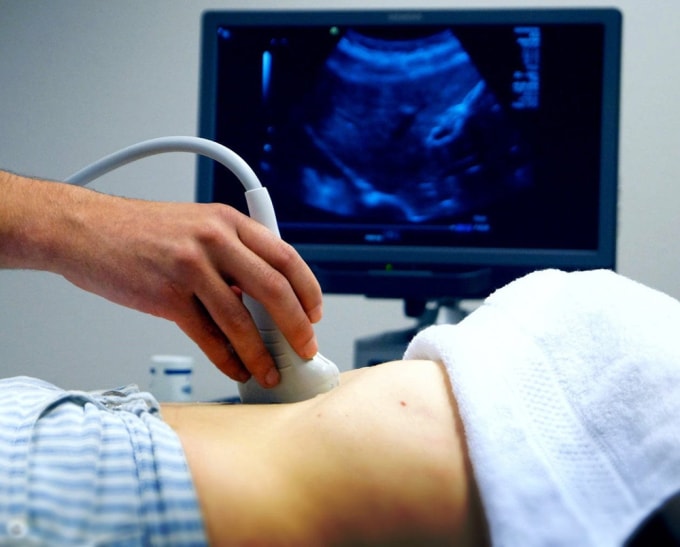

Sohu ngày 31/1 đưa tin sau khi bệnh nhân nam cao tuổi khám tại Bệnh viện Nhân dân thành phố Ngô Trung, tỉnh Ninh Hạ, người thân tra cứu kết quả trên cổng thông tin trực tuyến của bệnh viện và ngỡ ngàng thấy dòng chữ: "Siêu âm Doppler màu sản phụ khoa".

Kết quả siêu âm ghi nhận bệnh nhân có "thai sớm trong tử cung" (Early Intrauterine Pregnancy), "không loại trừ khả năng thai ngừng phát triển", kèm chi tiết tử cung tư thế ngả trước và kích thước túi thai.